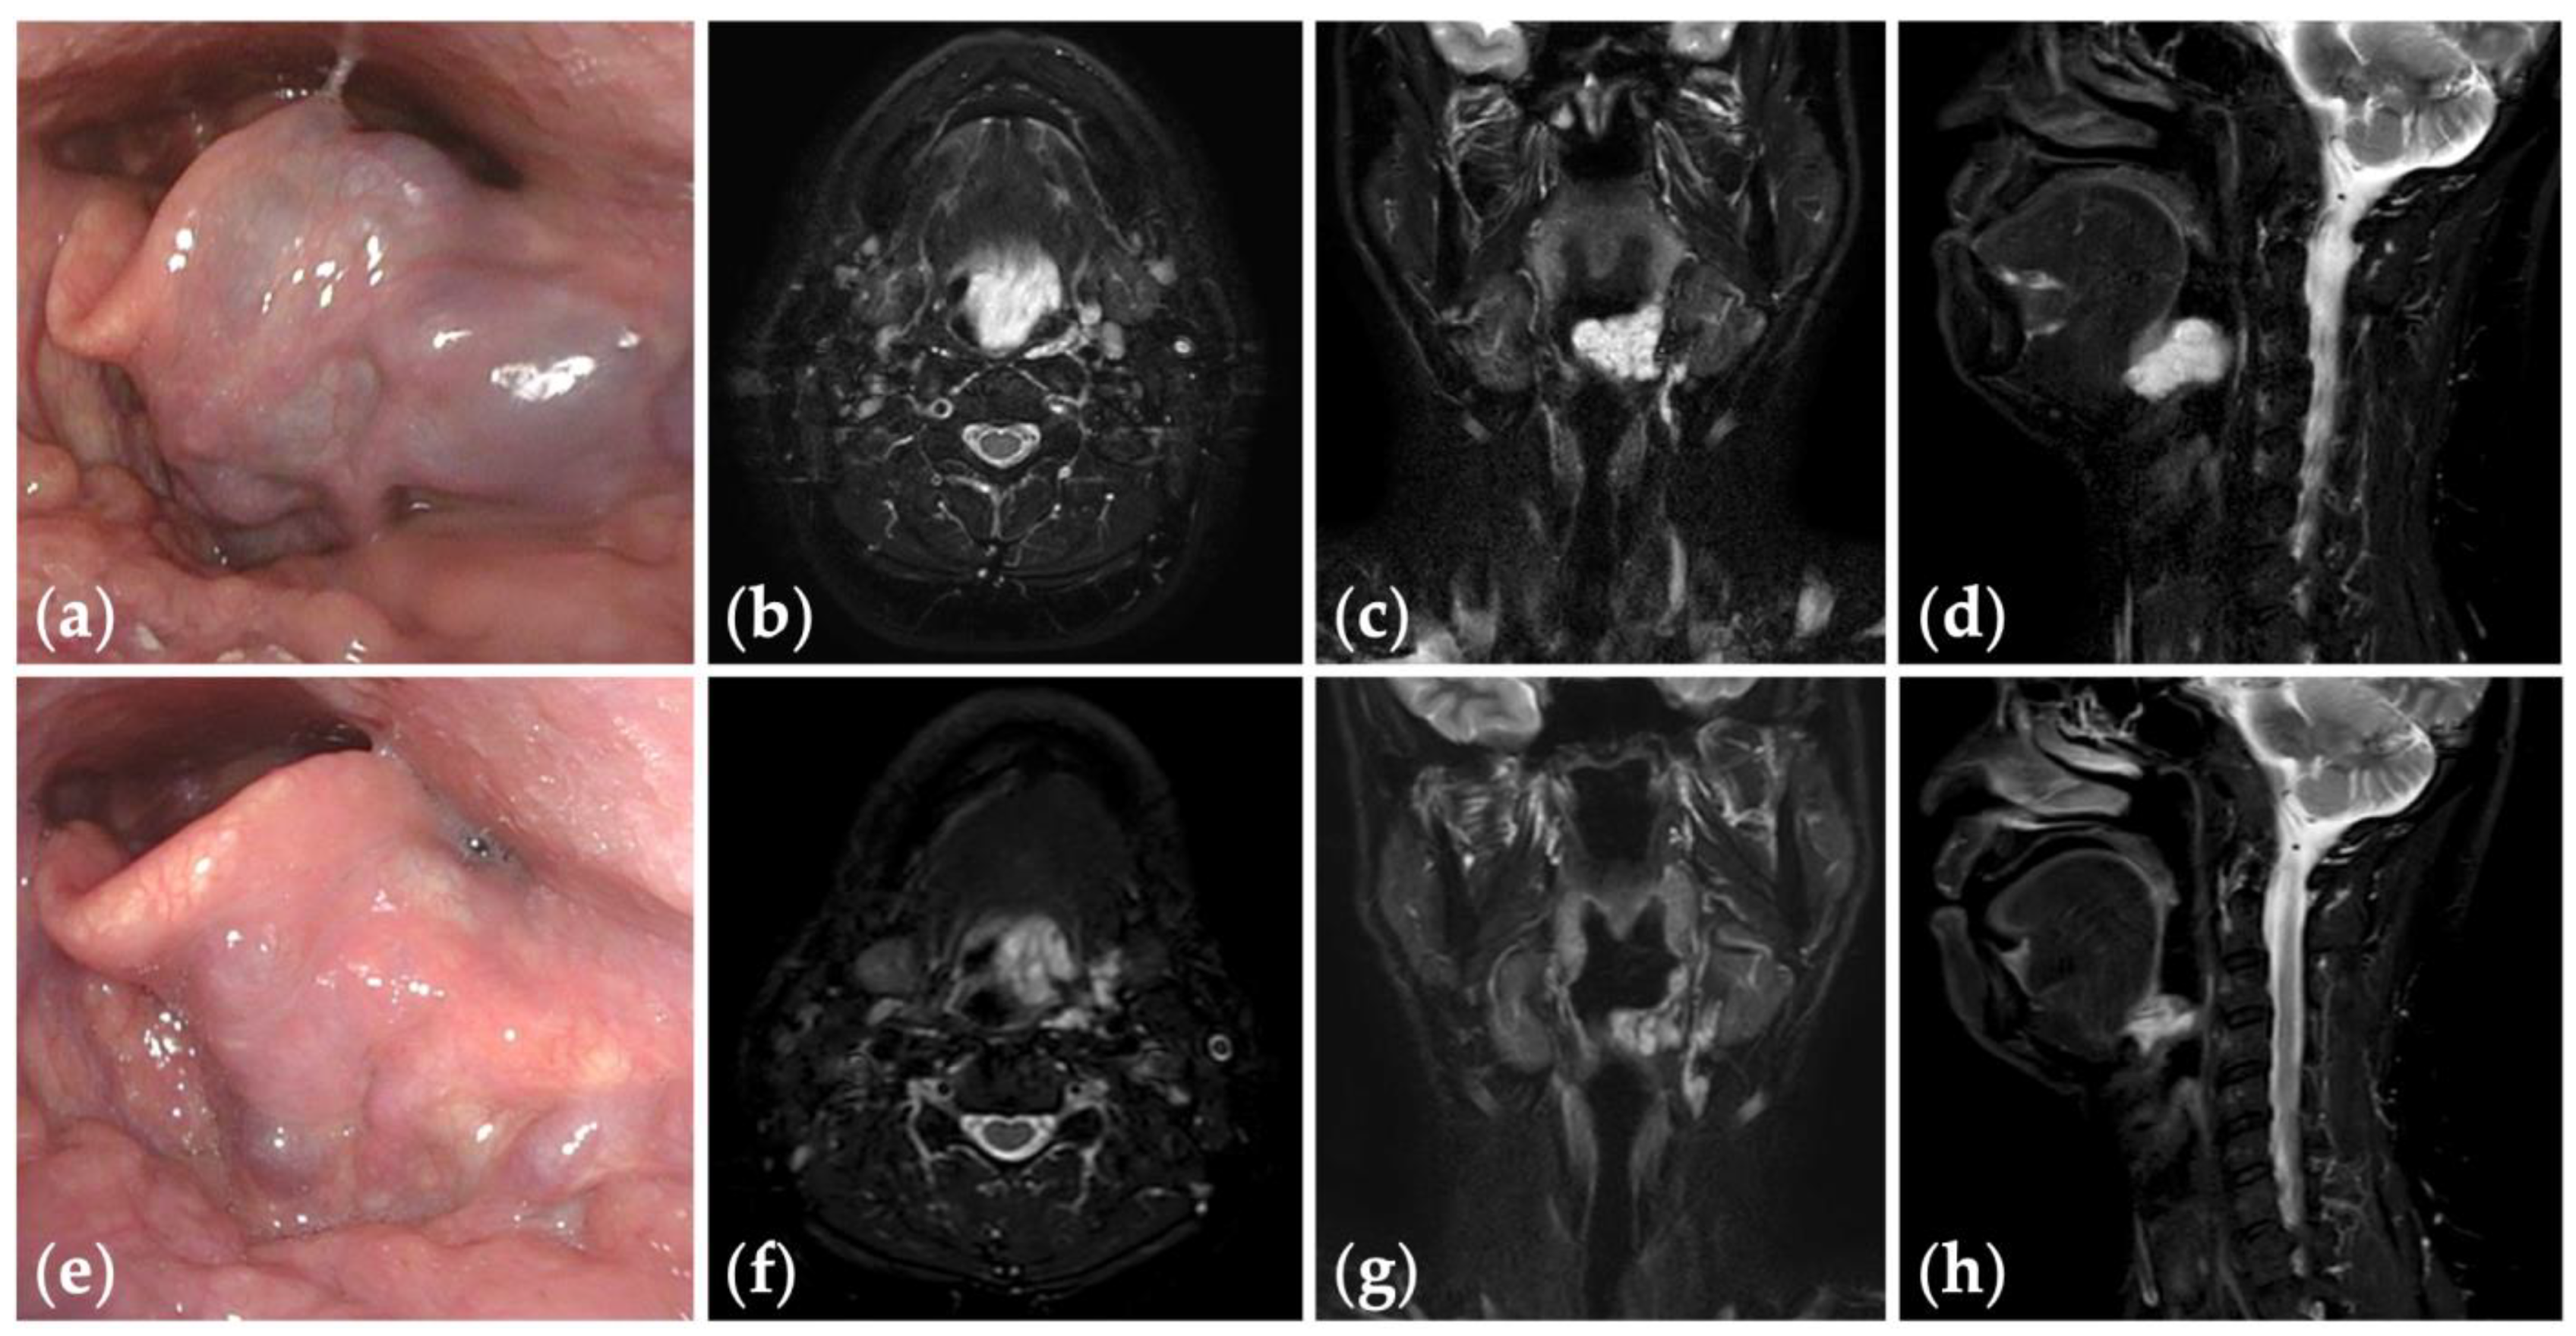

Patient 10 graded “excellent” for treatment outcomes after three sessions of fluoroscopy- and endoscopy-guided transoral sclerotherapy: (a) an initial endoscopic photograph of the epiglottis of a 43-year-old man with pharyngeal venous malformation, and (e) the latest endoscopic photograph six months after the final sclerotherapy session at the age of 45 years; (b–d) short tau inversion recovery T2-weighted magnetic resonance images before treatment, and (f–h) three years after the final sclerotherapy session at the age of 47 years.